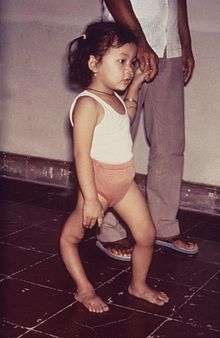

| |

| A man with a smaller right leg due to poliomyelitis | |

Residual complications of paralytic polio often occur following the initial recovery process.[14] Muscle paresis and paralysis can sometimes result in skeletal deformities, tightening of the joints and movement disability. Once the muscles in the limb become flaccid, they may interfere with the function of other muscles. A typical manifestation of this problem is equinus foot (similar to club foot). This deformity develops when the muscles that pull the toes downward are working, but those that pull it upward are not, and the foot naturally tends to drop toward the ground. If the problem is left untreated, the Achilles tendons at the back of the foot retract and the foot cannot take on a normal position. Polio victims that develop equinus foot cannot walk properly because they cannot put their heel on the ground. A similar situation can develop if the arms become paralyzed.[71] In some cases the growth of an affected leg is slowed by polio, while the other leg continues to grow normally. The result is that one leg is shorter than the other and the person limps and leans to one side, in turn leading to deformities of the spine (such as scoliosis).[71] Osteoporosis and increased likelihood of bone fractures may occur. An intervention to prevent or lessen length disparity can be to perform an epiphysiodesis on the distal femoral and proximal tibial/fibular condyles, so that limb's growth is artificially stunted, and by the time of epiphyseal (growth) plate closure, the legs are more equal in length. Alternatively, a person can be fitted with custom made footwear which corrects the difference in leg lengths. Other surgery to re-balance muscular agonist/antagonist imbalances may also be helpful. Extended use of braces or wheelchairs may cause compression neuropathy, as well as a loss of proper function of the veins in the legs, due to pooling of blood in paralyzed lower limbs.[44][72] Complications from prolonged immobility involving the lungs, kidneys and heart include pulmonary edema, aspiration pneumonia, urinary tract infections, kidney stones, paralytic ileus, myocarditis and cor pulmonale.[44][72]